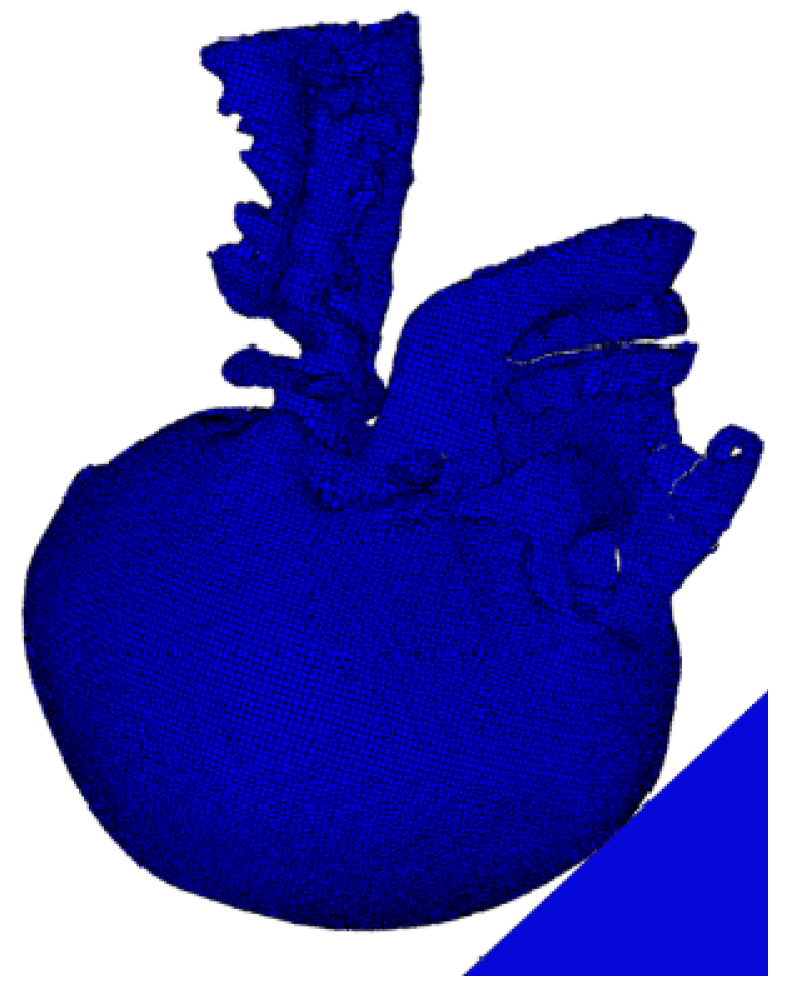

2.1. Finite Element Model of the Head

2.1.1. Model Construction